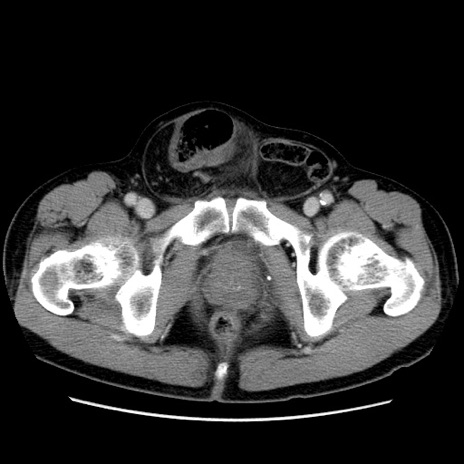

症例34(横断像)

【症例】60歳代 男性

【主訴】右鼠径部膨隆

【現病歴】1年程前より右鼠径部膨隆あり。自己にて還納可能だったため放置していた。3時間前より右鼠径部の脱出を認め、還納困難となり受診。

【既往歴】高血圧

【身体所見】右鼠径部に小児頭大の膨隆あり。弾性硬であり、用手還納は困難。左鼠径部にも膨隆を認める。脱出はなし。